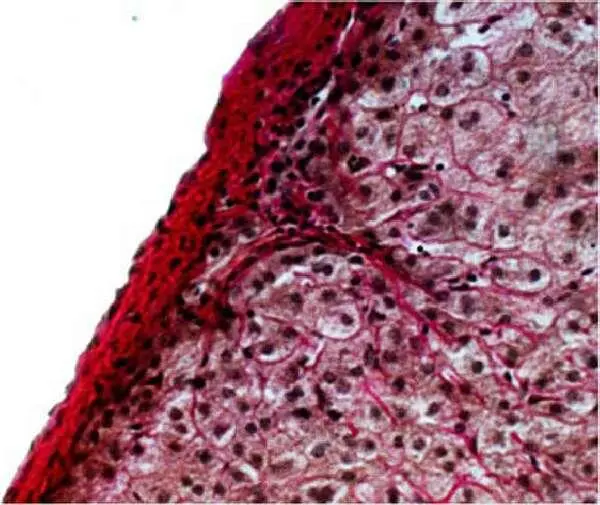

Рисунок 10 – Склероз капсулы печени; от капсулы отходят фиброзные тяжи, рассекающие паренхиму. Окр.: пикрофуксином. Х200.